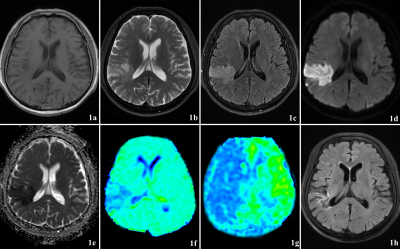

1901ffa1aec9dcdb3033acc1150564c9.png

患者为一名57岁男性,头晕和左肢运动无力约1天。

1a-1c:右侧颞叶脑组织肿胀,在T1WI、T2WI上呈轻度高信号,在T2-FLAIR上呈明显高信号;

1d-1e:DWI图像显示急性梗死病灶;1f:APTw显示APT减少区域,且APTw病灶与DWI病灶几乎一致;

1g:ASL显示大面积低灌注区域,存在明显的DWI/ASL不匹配;1h:3个月后随访的FLAIR图像大小与DWI几乎相同,表明没有缺血半影区。